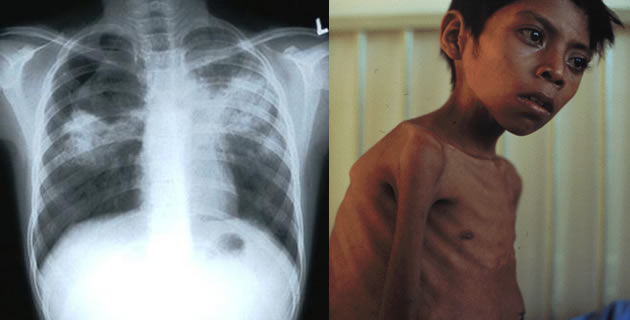

Se rijetko javlja prije puberteta, češće kod ženske djece, osobito poslije nekog pada opšte otpornosti organizma. Najčešće su zahvaćeni apikalni i posteriorni segmenti lobusa koji favorizuju rast bacila i diseminaciju limfo-hematogenim putem u toku primarne infekcije. Incijalni infiltrat je sklon širenju i kavernizaciji, pa i endotrahealnoj diseminaciji, ali za razliku od primarne TBC obično nema intratorakalne limfadenopatije. Klinički nastupa sa malim febrilnim stanjima koja dugo traju, a praćeno je sa obilnim noćnim znojenjem, umorom do malaksalosti, postepeno dolazi do pada na težini i javlja se bljedilo. Razvoj kazeozne nekroze, likvefakcije i kavernizacije može pratiti produktivni kašalj pa i hemoptizija. Auskultatorno se mogu čuti različiti zvučni fenomeni, ali se o njima više piše nego što se nađu u praksi.

Radiološki se u početku može otkriti infiltrat koji može biti okrugao, homogen, čvrst, inflaklavikularno ili apikalno. Infiltrat može zahvatiti i čitav lobus. Kaverne nastaju poslije likvefakcije, nekroze i ispražnjenja kazeoznih masa. Obično su debelih zidova, a ponekad se može pojaviti i zrak iznad tekućine. Tok bolesti je hroničan, progresivan i može trajati mjesecima i godinama. Prognoza nije loša, obično dolazi do kompletnog izlječenja.